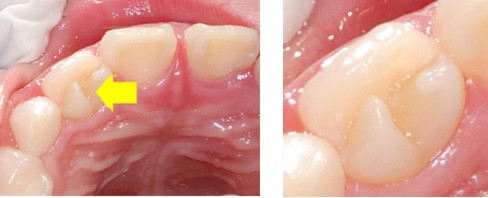

齒外齒

(Dens Evaginatus,後牙又稱 中央牙阜 Central Cusp,前牙稱作Talon cusp)

是一種亞洲人常見的牙齒形態發育異常,臨床特稱是好發於小臼齒咬合面,形成結節(tubercle)狀突起;

少數在前牙的例子,則是在舌側長出像鷹爪狀的突起。(如下圖)